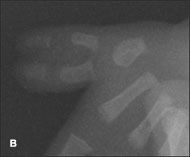

Complete duplication of the left thumb in a baby boy was noted at birth; a radiograph of the thumb showed 2 proximal and distal phalanges with 1 first metacarpal bone (A and B). He also had fusion and incomplete bony duplication of the right thumb; a radiograph of this digit showed normal proximal and distal phalanges plus a small tiny bony remnant of the proximal and distal phalanges of an accessory thumb (C and D).

The infant had no other apparent abnormalities. He had been born at term after a normal pregnancy and uncomplicated delivery. The mother had 2 sisters; each had 1 child with ulnar polydactyly-nubbin accessory digits on the little fingers.